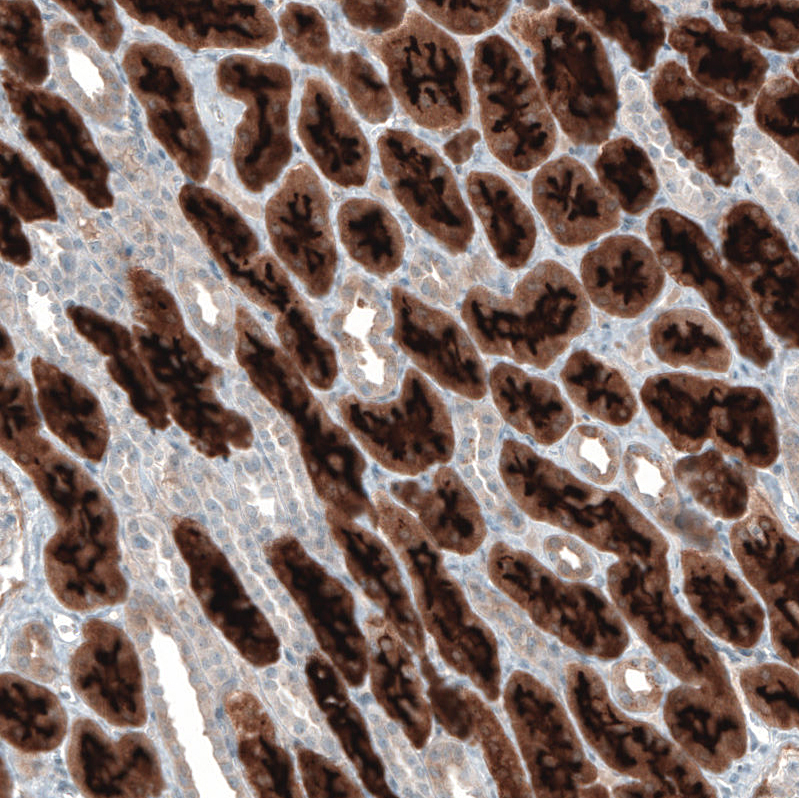

Product information "Anti-PDZK1"

Protein function: A scaffold protein that connects plasma membrane proteins and regulatory components, regulating their surface expression in epithelial cells apical domains. May be involved in the coordination of a diverse range of regulatory processes for ion transport and second messenger cascades. In complex with SLC9A3R1, may cluster proteins that are functionally dependent in a mutual fashion and modulate the trafficking and the activity of the associated membrane proteins. May play a role in the cellular mechanisms associated with multidrug resistance through its interaction with ABCC2 and PDZK1IP1. May potentiate the CFTR chloride channel activity. Required for normal cell-surface expression of SCARB1. Plays a role in maintaining normal plasma cholesterol levels via its effects on SCARB1. Plays a role in the normal localization and function of the chloride-anion exchanger SLC26A6 to the plasma membrane in the brush border of the proximal tubule of the kidney. May be involved in the regulation of proximal tubular Na(+)-dependent inorganic phosphate cotransport therefore playing an important role in tubule function. [The UniProt Consortium] Buffer: 40% glycerol and PBS (pH 7.2). 0.02% sodium azide is added as preservative. Highest antigen sequence identity to mouse: 91% and to rat: 92%

| Application: | ICC, IHC, WB |